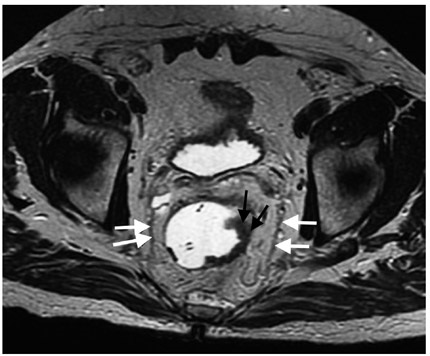

Los elementos que deben ser valorados en una resonancia magnética para cáncer rectal primario son el estadio, la profundidad de la invasión más allá de la muscular propia y la relación del tumor con la fascia mesorrectal (figura 1), la fascia presacra (figura 2), el esfínter anal y las paredes de la pelvis (15).

La fascia mesorrectal es un punto de referencia anatómica para la evaluación diagnóstica de la extensión tumoral (33,34); este es el factor más importante en cuanto al pronóstico (8) ya que el compromiso de la fascia mesorrectal aumenta el riesgo de recurrencia local y a distancia (8). La fascia mesorrectal corresponde a la capa visceral de la fascia intrapélvica (15). Compone una unidad anatómica diferente al rodear el recto y contener la grasa mesorrectal, ganglios y vasos linfáticos (15). En imágenes de alta definición con información T2 se visualiza como una imagen hipointensa lateral al recto (figura 1) (15).

La relación entre la fascia mesorrectal y el tumor es esencial para la planeación quirúrgica (15). En histología, una distancia mayor a 1 mm entre el tumor y el margen de resección se correlaciona con una menor probabilidad de recurrencia local (15,35). A medida que la distancia sea menor, mayor será la posibilidad de compromiso (8,36). Por este motivo, en secuencias con información T2 de alta resolución, una distancia menor de 1 mm entre el tumor y la fascia mesorrectal indica compromiso; sin embargo, este margen puede cambiar según los diferentes centros (8,15,37-39). Esta medida puede ser tomada desde cualquiera de los siguientes sitios: a) el margen del tumor desde su extensión más allá de la muscular propia, b) depósitos tumorales en el mesorrecto, c) trombo tumoral al interior de una estructura vascular o d) un ganglio linfático de aspecto tumoral (8,15).